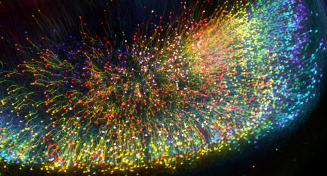

To overcome these barriers, the team developed a new tissue clearing solution, OPTIClear. OPTIClear selectively adjusts the optical properties of tissue without damaging or changing their structural components. Combined with fluorescent staining and other tissue processing methods, the team created a simple yet versatile tool for the study of microscopic structures in the human brain. Nerve cells, glial cells, and blood vessels were visualized in exquisite detail, with their 3D relationship determined. For example, the team performed 3D morphological analysis on human brainstem dopaminergic neurons in the millimetre scale, and imaged more than 3,000 large neurons in the human basal forebrain in merely five days, which normally is extremely laborious and takes at least three weeks. These neurons have been implicated in neurological and psychiatric diseases such as dementia and depression; the promising results suggest that this novel method is applicable to future research on these conditions. More remarkably, OPTIClear can also be applied in both archived (>30 years) and clinical specimens.